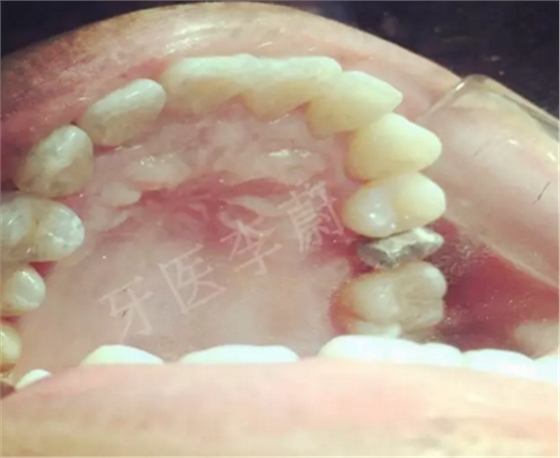

15牙冠制備中

15牙硅橡膠取模